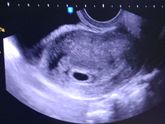

Пришла к своему врачу платно, т.к. записи уже и на май закрыты) завели карточку, все померили и расспросили) Моя врач была приятно удивлена, что беременность наступила естественным путем, ведь последний раз когда мы с ней виделись, она давала мне направление … Читать далее